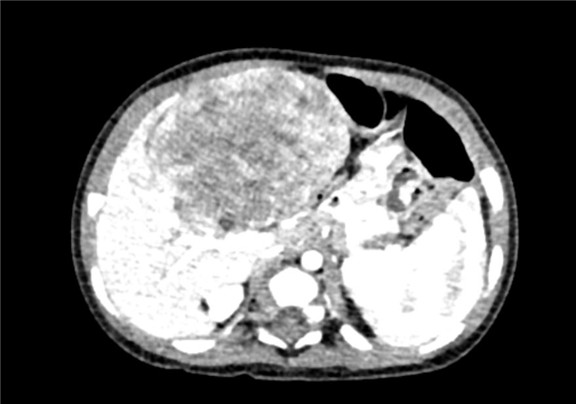

术前CT检查:

动脉期

静脉期